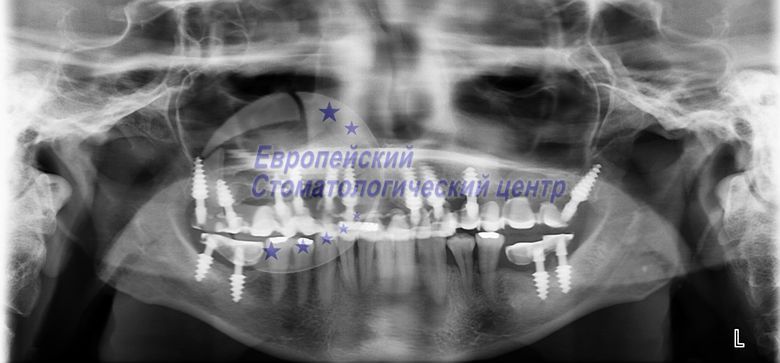

ОЗУ до операції

В даній клінічній ситуації були скарги на відсутність зубів, на естетичний дефект. На ортопантомограмме (ОЗУ) видно періодонтітние зуби які підлягають видаленню. Так само бачимо недостатній обсяг кісткової тканини на верхній щелепі. І неможливу установку імплантатів класичним способом без відновлення обсягу кістки. Було прийнято рішення видалити всі інфіковані зуби на верхній щелепі з негайною установкою одноетапних і базальних імплантатів в одне відвідування в лунки видалених зубів. Лунки видалених зубів оброблялися ербіевим лазером. Через день після операції встановлено тимчасові коронки. Через чотири місяці після операції тимчасові коронки помінялися на постійні з біологічно інертного матеріал РЕЙОК.